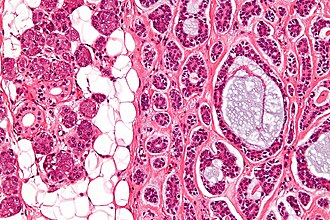

Adenoid cystic carcinoma. H&E stain. | |

| LM | cribriform architecture (other patterns: solid, cords, (bilayered) tubules), cystic spaces filled with basophilic material, scant cytoplasm in most cells, nucleus - small, hyaline stroma |

- Cribriform architecture or pseudoglandular spaces (classic pattern) - important feature.

- Other patterns: solid, cords, (bilayered) tubules.

- Cystic spaces filled with basophilic material (that is PAS +ve) - key feature.

- Scant cytoplasm in most cells (myoepithelial cells) - clear/eosinophilic.

- Moderate eosinophilic cytoplasm in the (rare) ductal cells.

- Nucleus - small.

- May be angulated (carrot-shaped) - myoepithelial cells; round/ovoid in ductal cells.

- Hyaline stroma.